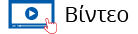

• την ηλικία (παρουσιάζεται συνήθως στην ηλικία των 65 ετών και η συχνότητα αυξάνεται με την πάροδο της ηλικίας)

Σύμφωνα με τα διεθνή στατιστικά δεδομένα, ένας στους δέκα άνδρες, θα αναπτύξει στον προστάτη του κακοήθεια.

Στατιστική για τον καρκίνο του προστάτη στην Αγγλία το 2005